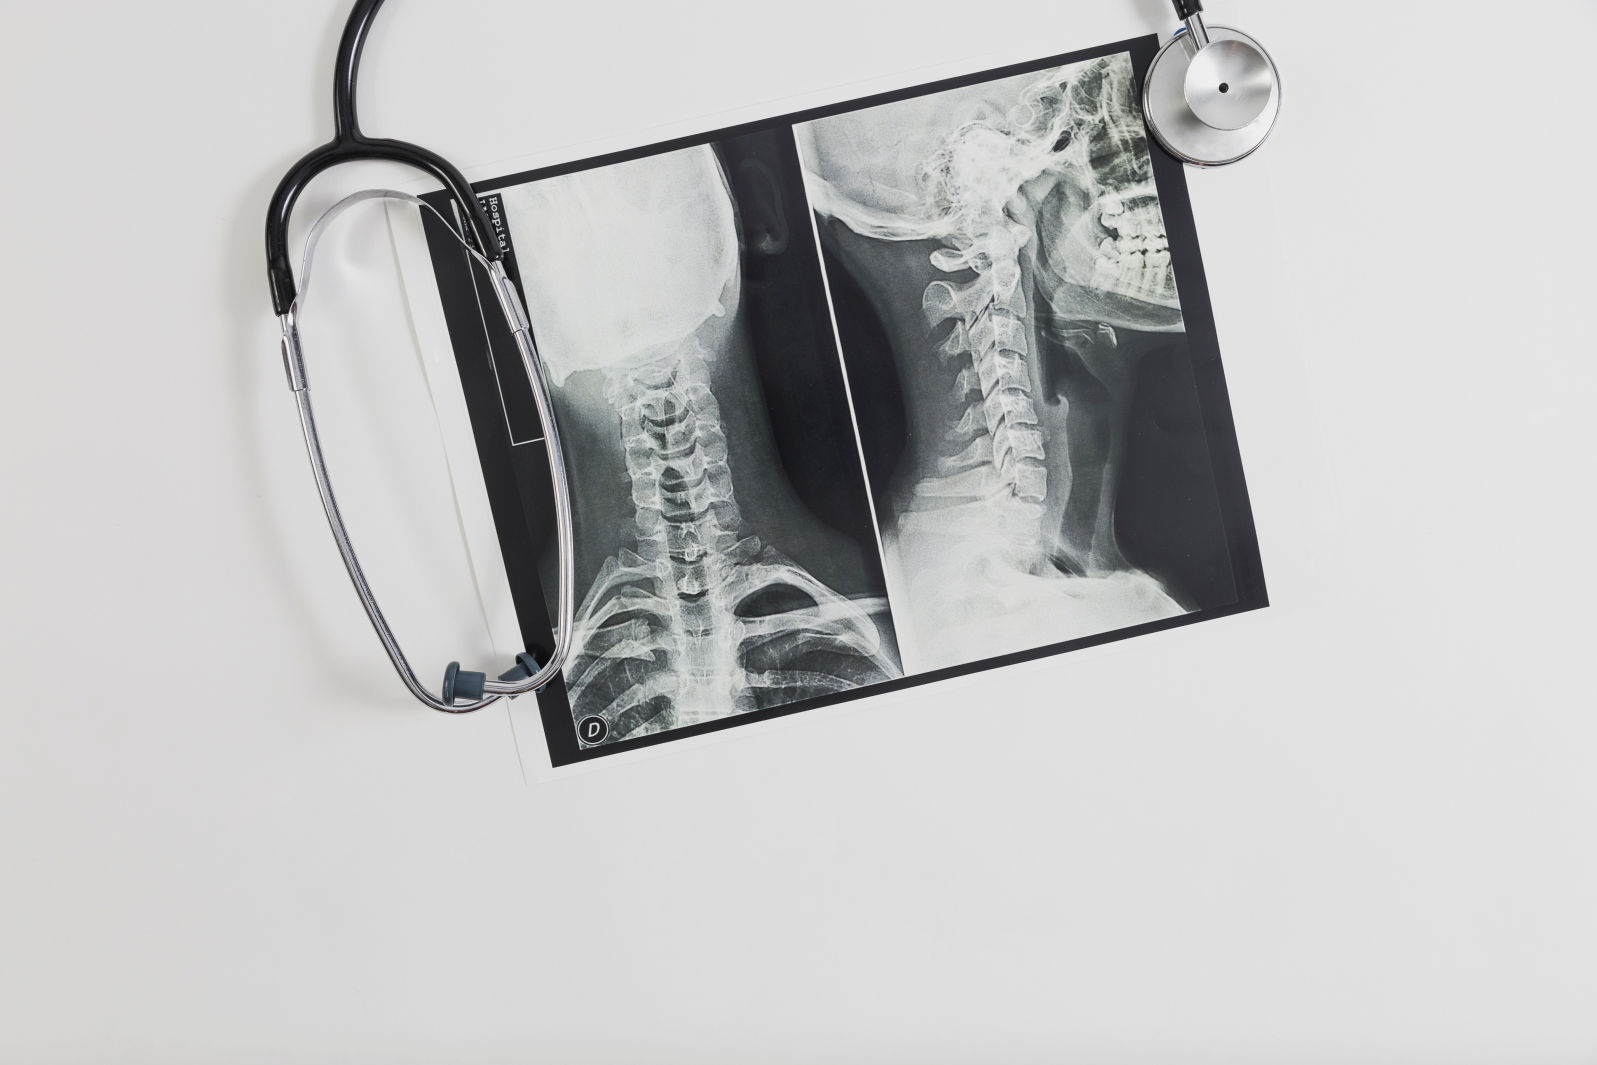

Abordajes regenerativos para la reparación del cartílago en el tratamiento de la osteoartritis

Según la Organización Mundial de la Salud, la osteoartrosis (OA) sintomática afecta al 9.6% de los hombres y al 18% de las mujeres mayores de 60 años alrededor del mundo, observándose que el 80% de los pacientes con OA presentan alguna limitación del movimiento, el 25% con discapacidad.